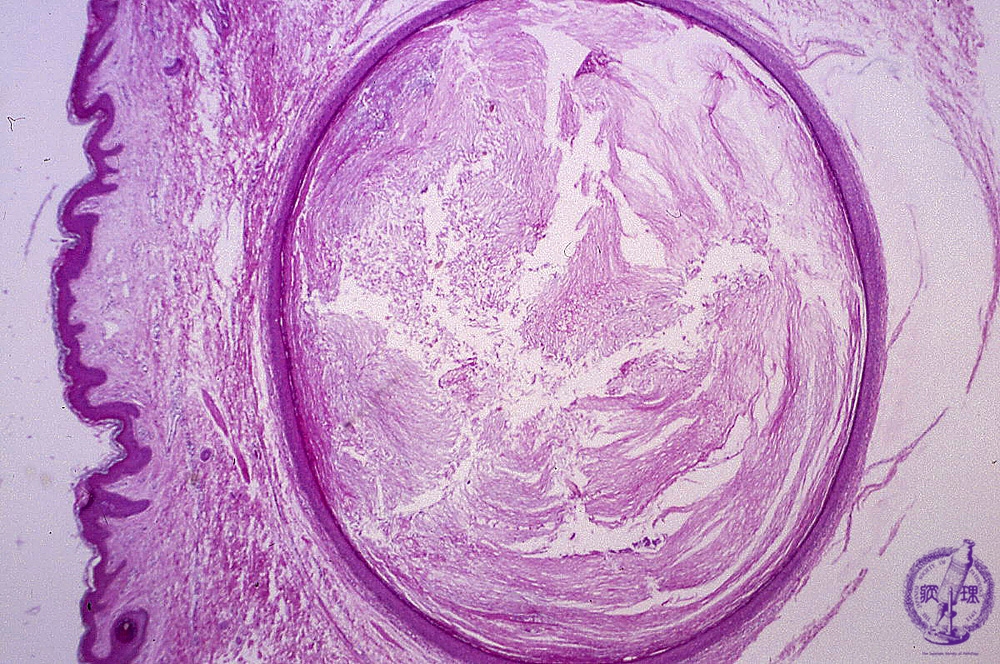

Microscopic findings: The cyst is filled with keratinizing materials. The wall does not contain skin appendages.